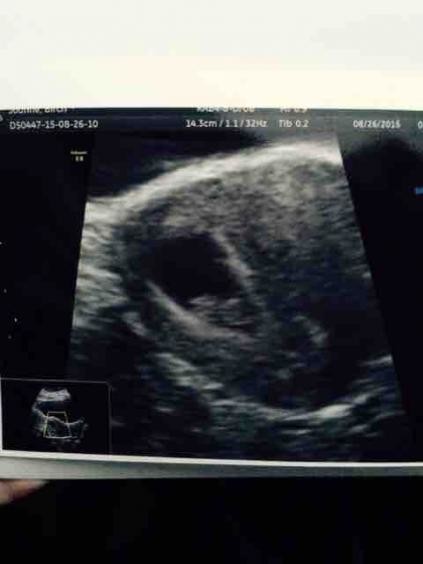

A dating scan is usually the first ultrasound scan you will have when pregnant . The main purpose is to establish the number of weeks you are pregnant and make an estimated date of expected delivery . This first early ultrasound scan also provides you and your consultant with additional important information, such as the number of babies you are . . .

This early pregnancy dating scan (ante-natal scan ) is useful for those who: Are experiencing pain or bleeding in the pregnancy Had a previous miscarriages Had a previous ectopic pregnancy Are unsure of date of last menstrual period And for those who need reassurance prior to their NHS scan , now usually performed after 12 weeks .